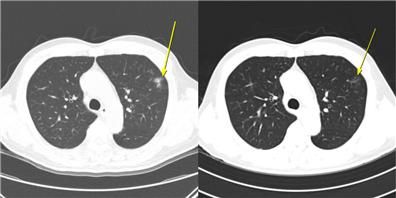

[그림, 무증상 일시적 면역관련 폐렴 사례: 이 환자는 AteBeva 치료 3개월째 시행한 저선량 흉부 CT(왼쪽)에서 폐 주변부에 미세 염증성 음영이 나타났으나, 6개월째 CT(오른쪽)에서는 자연적으로 소실되는 양상을 보였다. 치료는 지속됐으며, 이후 부분 관해(PR)를 달성했고 총 19.7개월간 무진행 생존(PFS)을 유지했다]